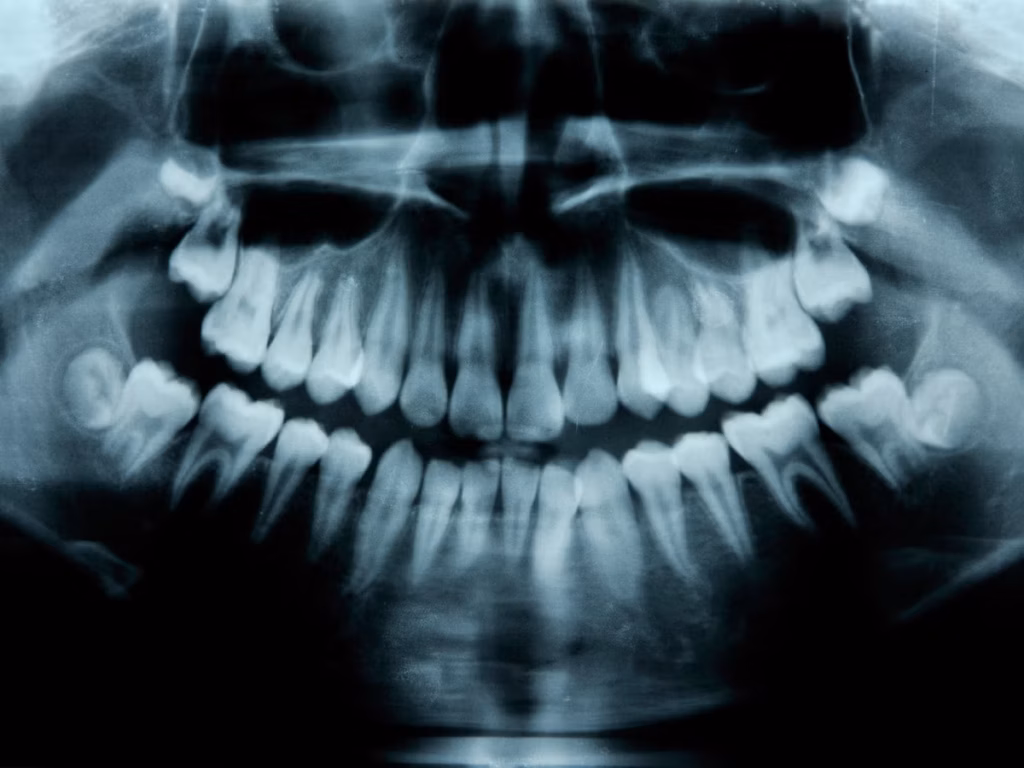

Вчені знайшли спосіб виростити нові зуби у дорослих людей

Дослідницька група з Японії під керівництвом Katsu Takahashi розпочала клінічні випробування препарату, здатного стимулювати зростання нових зубів у людей. Препарат впливає ген USAG-1, який, як встановили вчені, обмежує природне зростання зубів.

Дослідження ґрунтується на відкритті, що у людей існує зародковий третій набір зубів, який зазвичай не розвивається. Дане відкриття підтверджується наявністю гіпердонтії у 1% населення – стану, при якому зростає більше стандартного набору зубів.

Робота японських вчених розпочалася з експериментів на мишах у 2021 році, результати яких були опубліковані в журналі Scientific Reports. Дослідники розробили антитіла, які блокують білок, синтезований геном USAG-1, що призвело до успішного зростання додаткових зубів у гризунів.

Новий препарат особливо перспективний для лікування анодонтії — генетичного захворювання, при якому не формуються всі зуби, що стосуються близько 1% людей. Згідно з публікацією 2023 року в журналі Regenerative Therapy, цей метод може стати “проривом у лікуванні аномалій зубів у людей”.

Такахасі, завідувач відділення стоматології та щелепно-лицьової хірургії в Медичному дослідницькому інституті при лікарні Китано в Осаці, працює над цією технологією з аспірантури. За його словами, за успішного завершення клінічних випробувань препарат може бути доступний для широкого застосування до 2030 року.

Нова технологія пропонує альтернативу традиційним методам протезування та імплантації, дозволяючи відновлювати втрачені зуби природним шляхом.